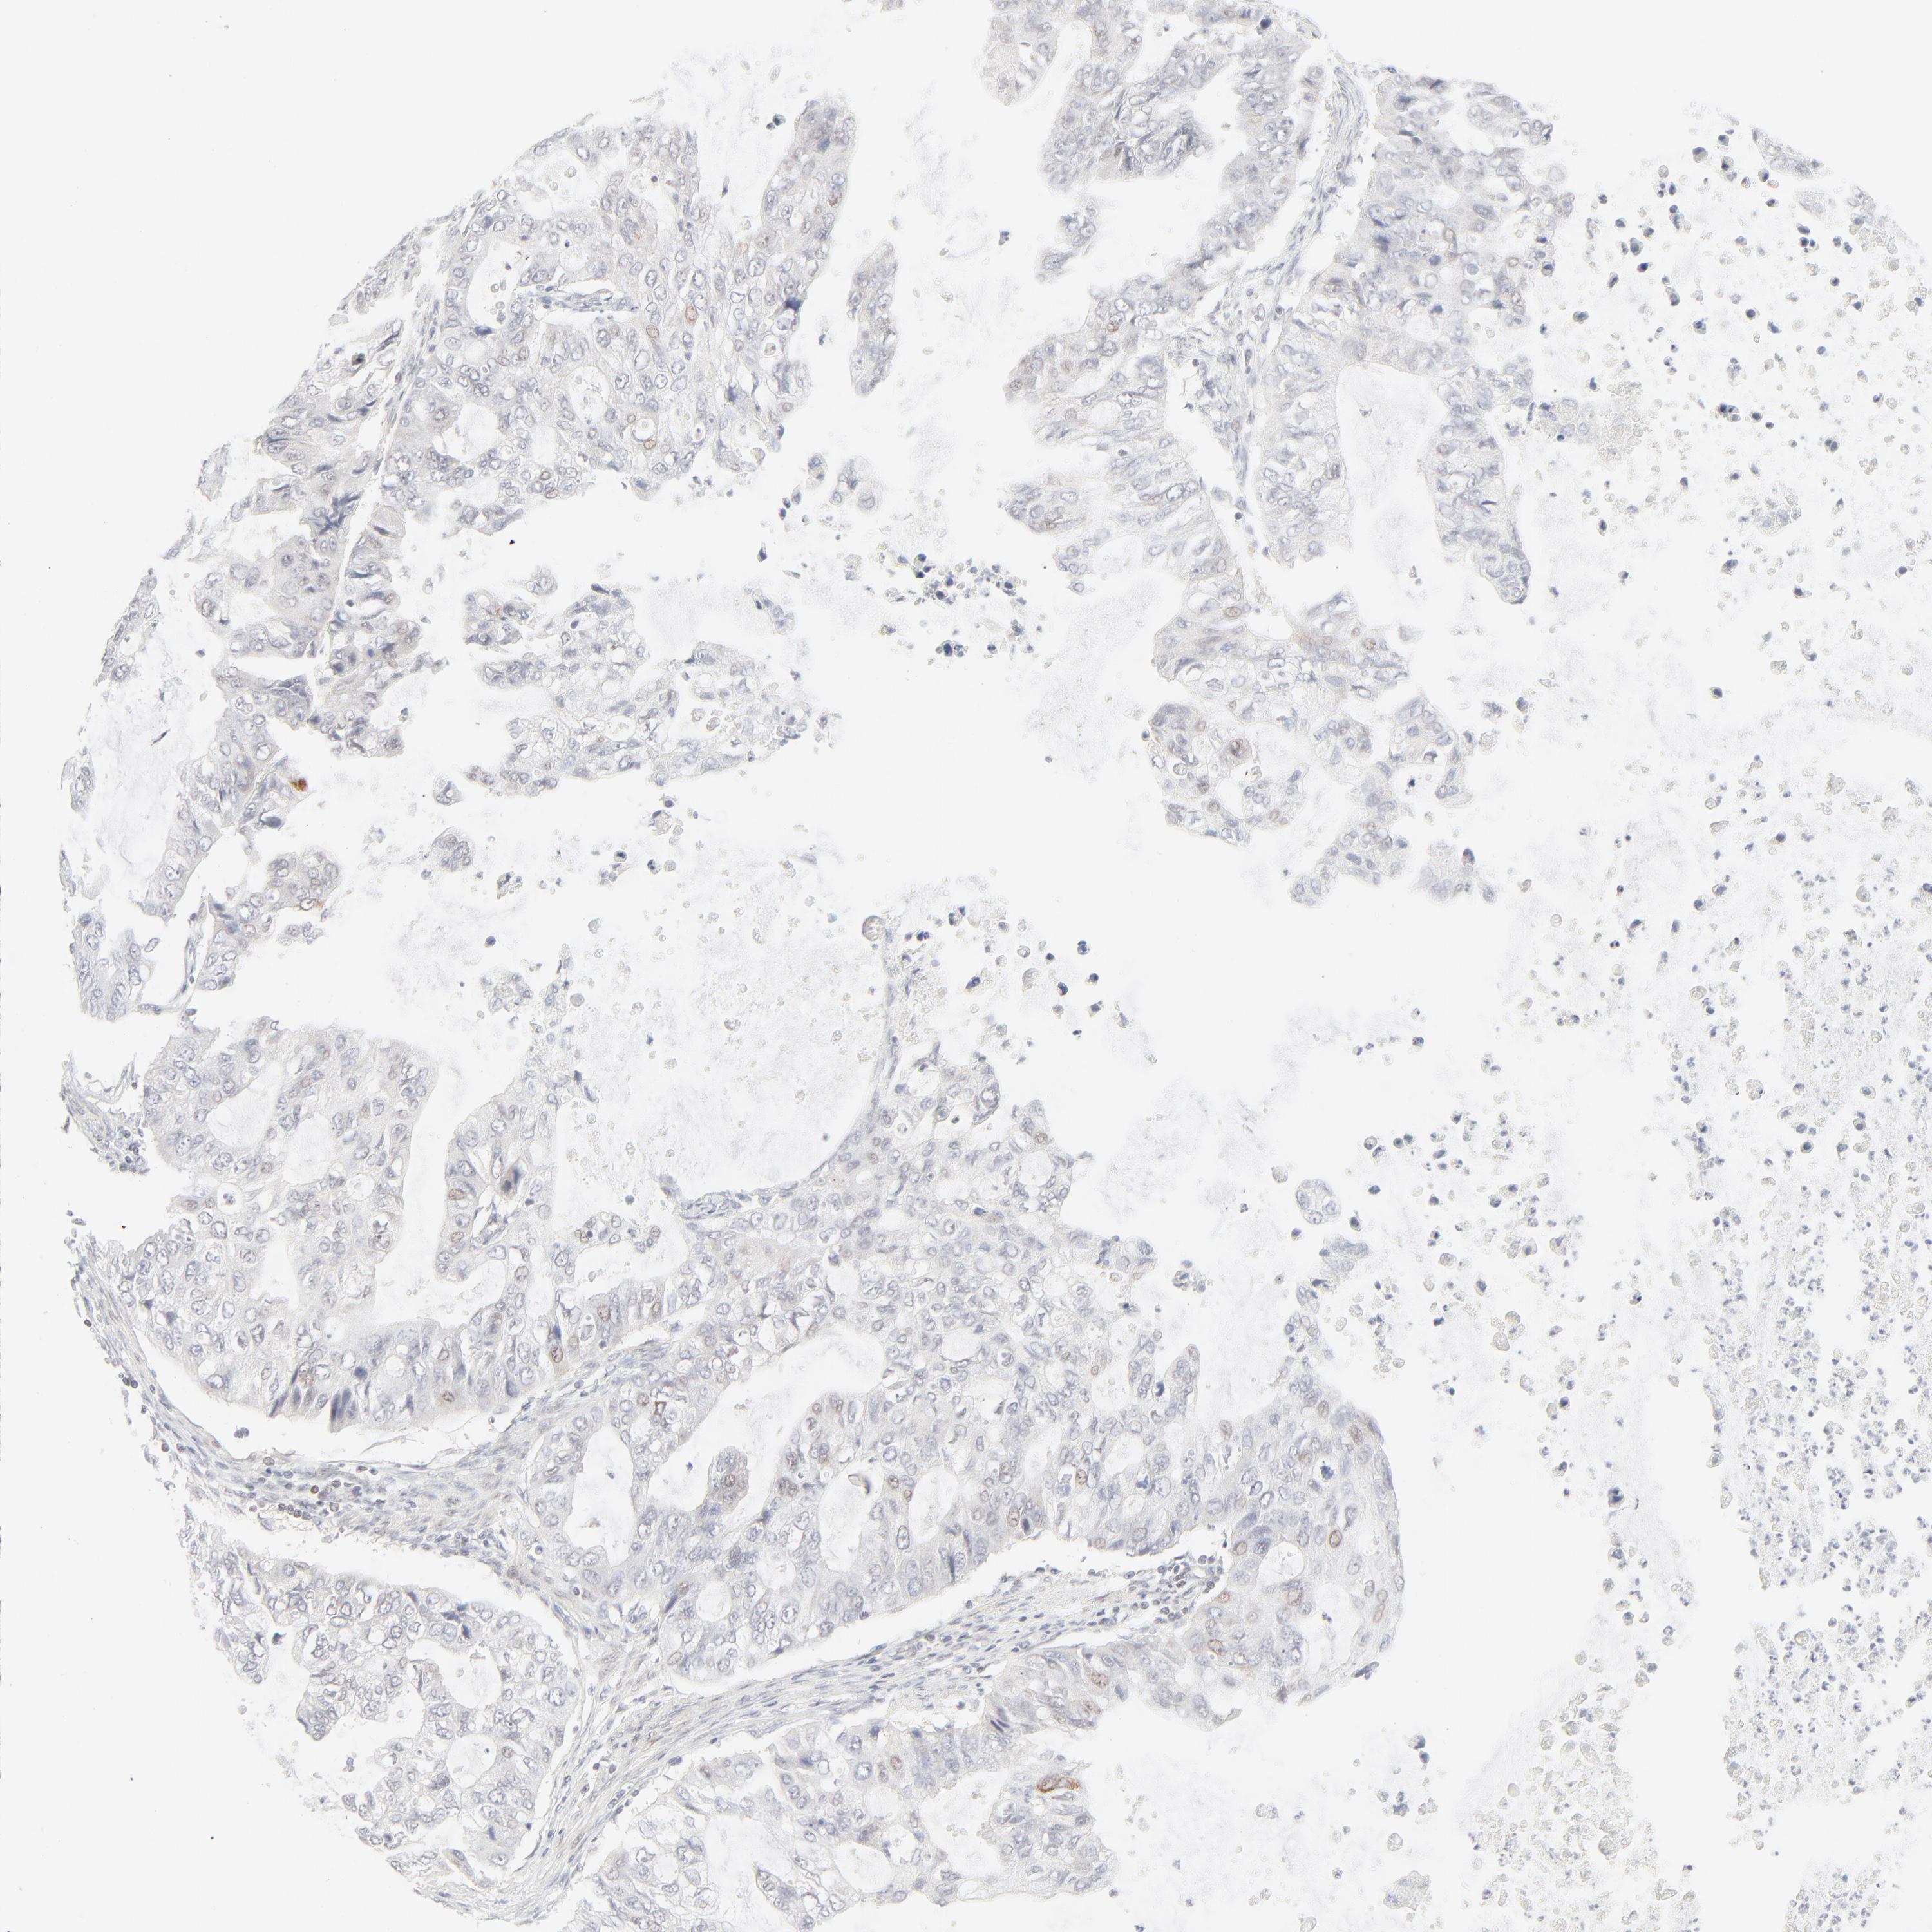

STOMACH CANCER - Protein expressioni

A mouse-over function shows sample information and annotation data. Click on an image to view it in a full screen mode. Samples can be filtered based on level of antibody staining by selecting one or several of the following categories: high, medium, low and not detected. The assay and annotation is described here.

Note that samples used for immunohistochemistry by the Human Protein Atlas do not correspond to samples in the TCGA dataset.

Antibody stainingi

Antibody staining in the annotated cell types in the current human tissue is reported as not detected, low, medium, or high, based on conventional immunohistochemistry profiling in selected tissues. This score is based on the combination of the staining intensity and fraction of stained cells.

Each image is clickable and will lead to virtual microscopy that enables deeper exploration of all samples and also displays staining intensity scores, fraction scores and subcellular localization as well as patient and tissue information for each sample.

Antibody HPA048321

Antibody CAB003843

Staining

High

Medium

Low

Not detected

Intensity

Strong

Moderate

Weak

Negative

Quantity

>75%

75%-25%

<25%

None

Location

Nuclear

Cytoplasmic/membranous

Cytoplasmic/membranous,nuclear

Adenocarcinoma, NOS